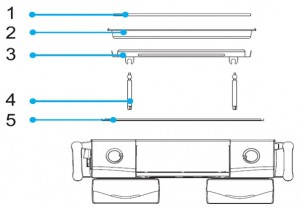

سینی های انکوباتور:

۱٫تشک نوزاد که معمولا از جنس اسفنجی است.

۲٫سینی نوزاد که محل قرار گیری نوزاد است

۳٫سینی کشوئی که برای نگه داشتن سینی نوزادتعبیه شده و به صورت ریلی می باشد.

۴٫پایه های سینی ریلی (در صورت درست جا نخوردن پایه ها امکان دارد به نوزاد صدمه وارد شود.)

۵٫سینی که نوزاد را از محل گرم کننده جدا می کند.